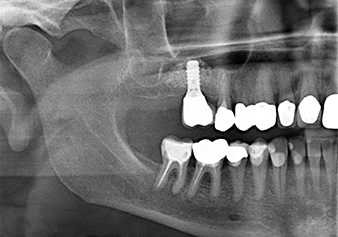

Une patiente de 49 ans, non fumeuse et sans antécédents médicaux remarquables, a été orientée vers notre cabinet de chirurgie orale pour l’extraction chirurgicale de la dent 16 préalable à la pose d’un implant. Après l’extraction, la patiente a rencontré de légers problèmes de sinusite, à la suite de quoi nous avons commencé par attendre six mois avant de prendre la mesure. À l’endroit prévu pour la pose de l’implant, l’os résiduel mesurait 3-4 mm de haut (Fig. 1 et 2).